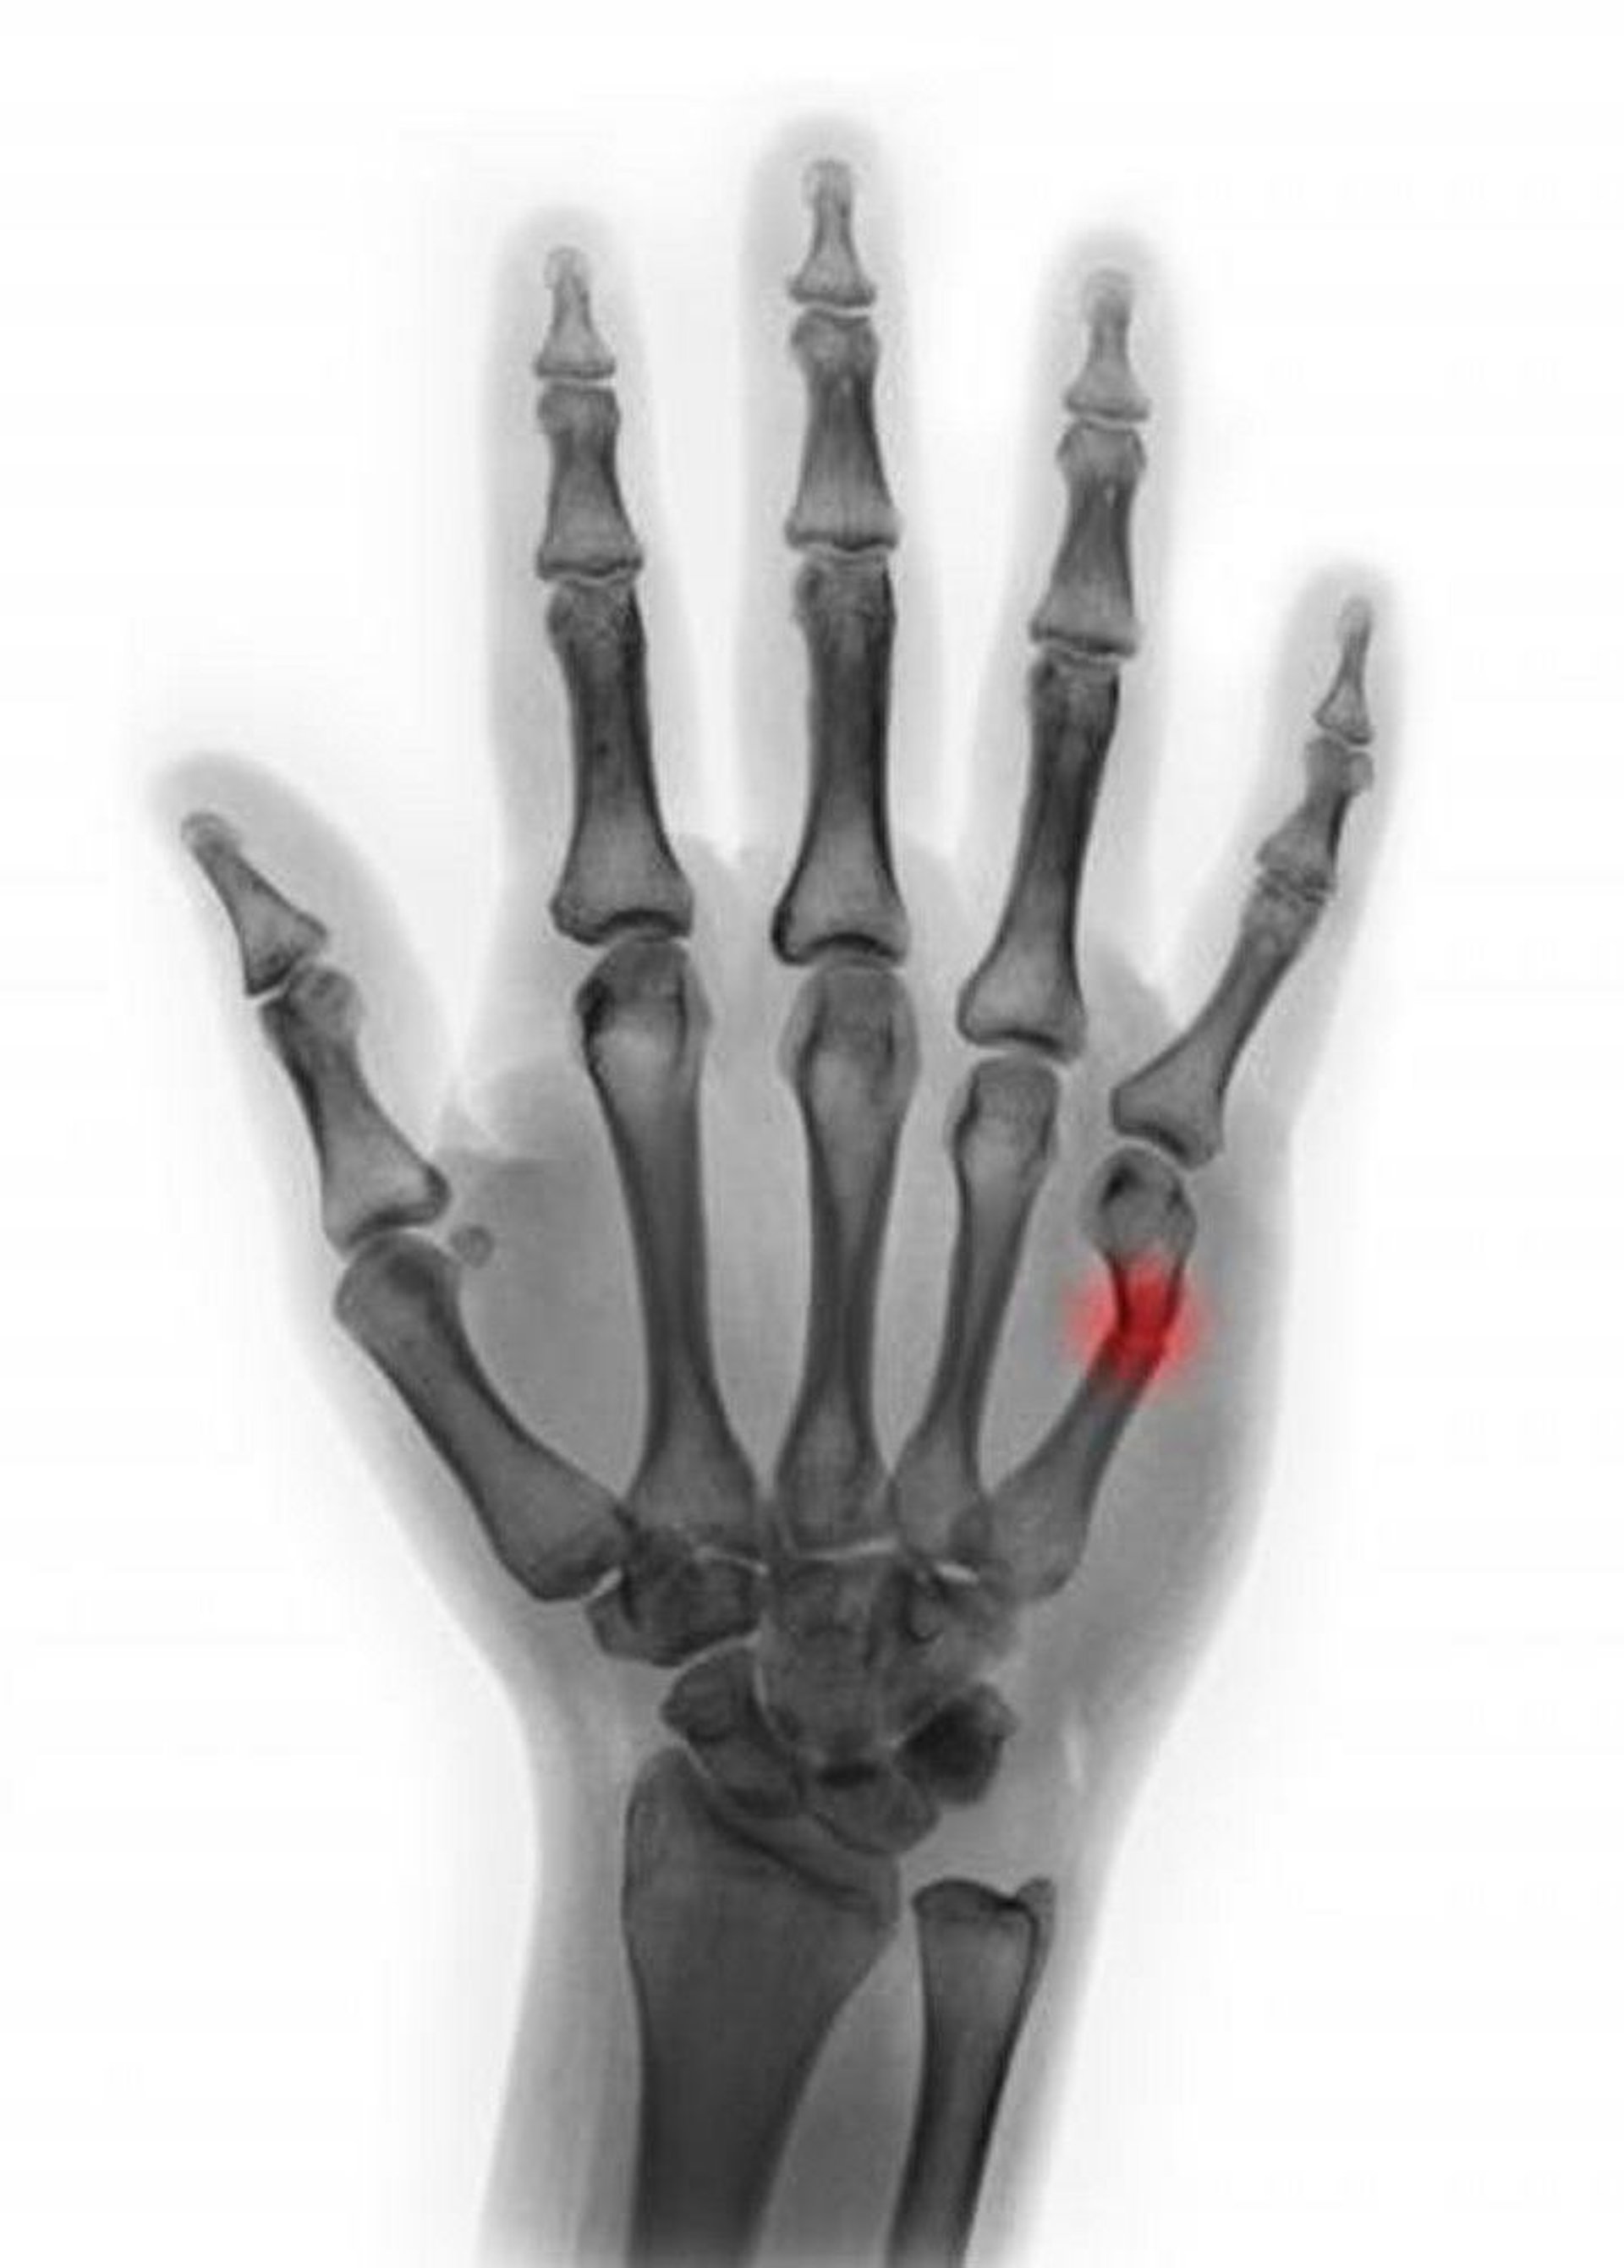

Fracture of the 5th Metacarpal Neck

This colored radiograph shows a fracture of the 5th metacarpal neck. In this view, angulation appears to be < 45°, suggesting that reduction is not necessary.